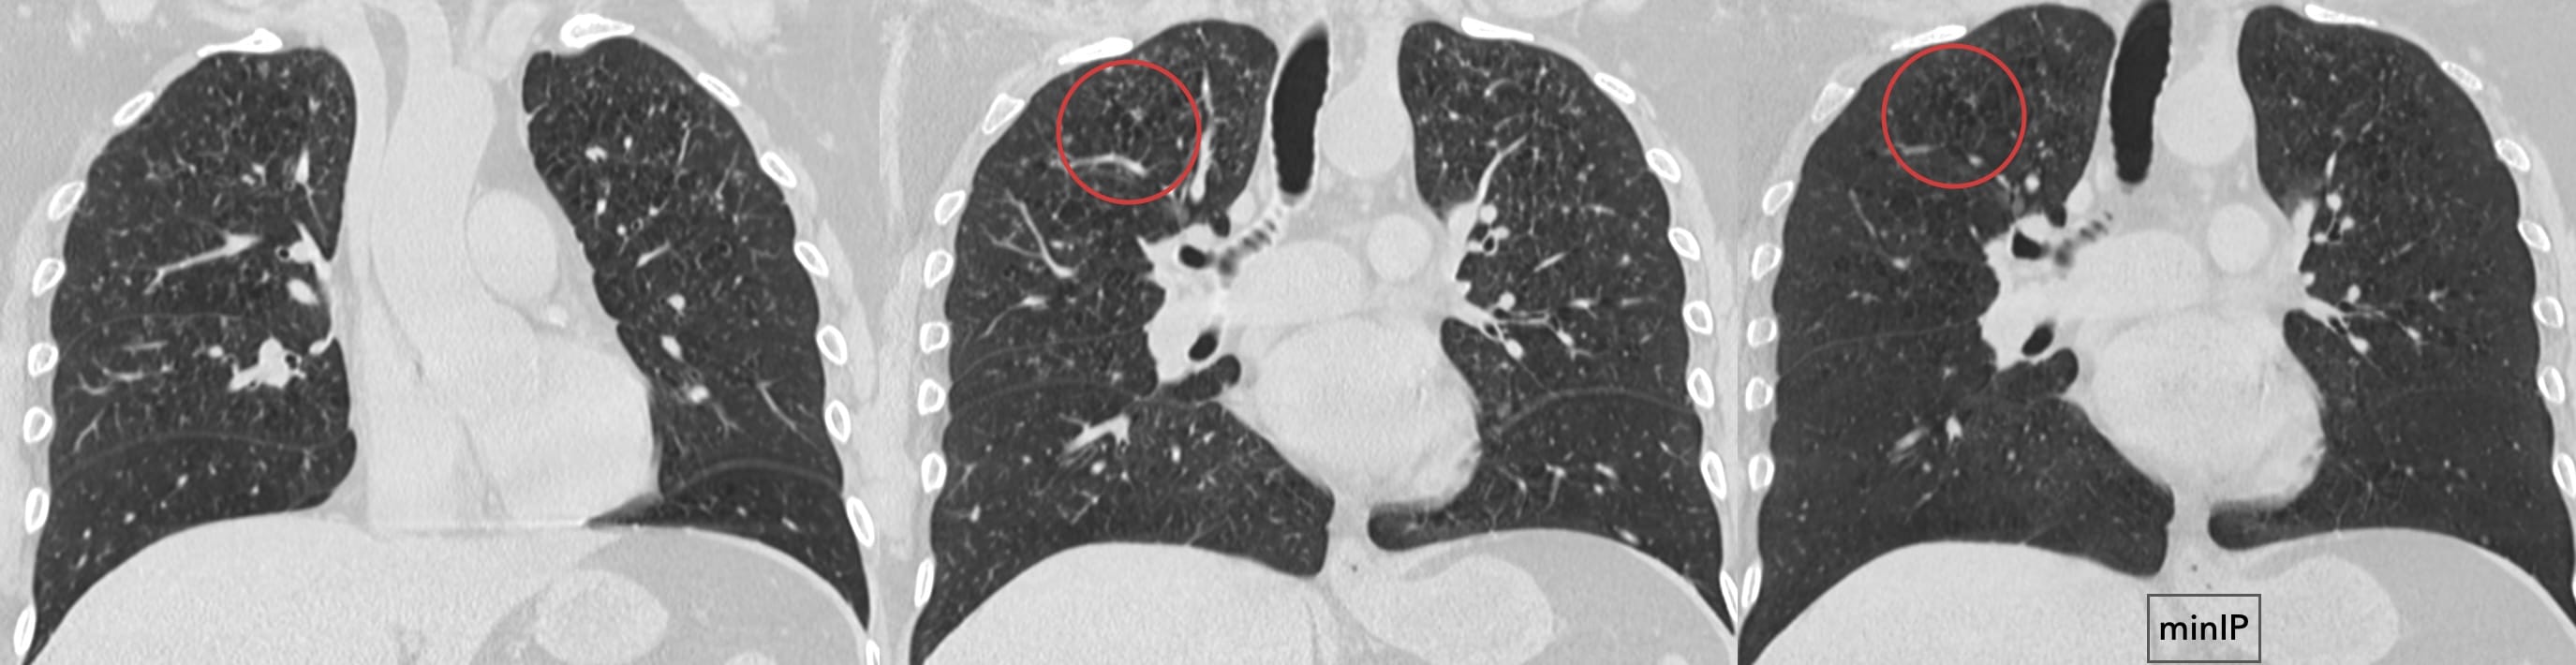

Note: bronchial wall thickening

Note the predominant involvement of the upper lungs.

The very definition of an Aunt Minnie